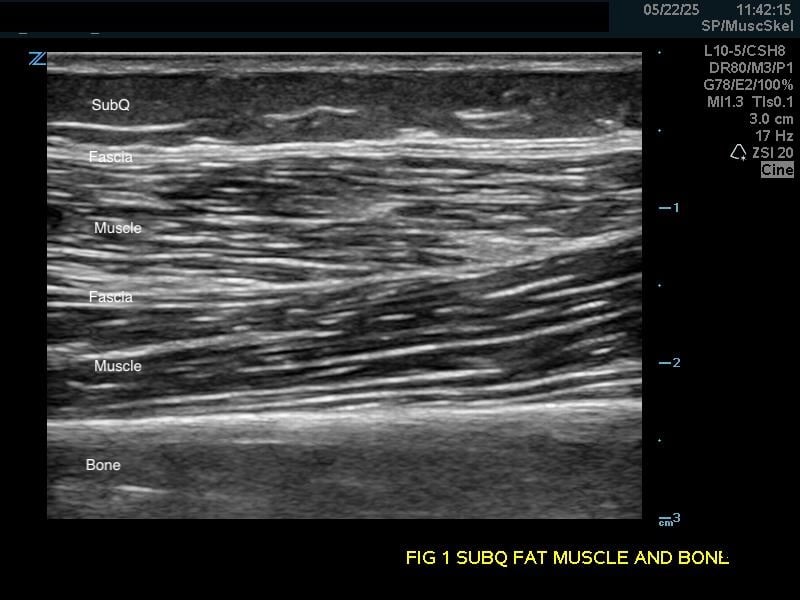

Figure 1b.

Transverse view.

Soft Tissue

Subcutaneous fat: Relatively hypoechoic with thin septations of connective tissue. The thickness of this layer varies and may require increasing the depth setting of your machine.

Muscle: Longitudinally, appears as slabs of striated hypoechoic tissue contained within the thin hyperechoic lines of fascia. Viewed transversely, muscle striations or septa appear dotted and punctate or form short lines. Fascial lines separate muscle compartments.